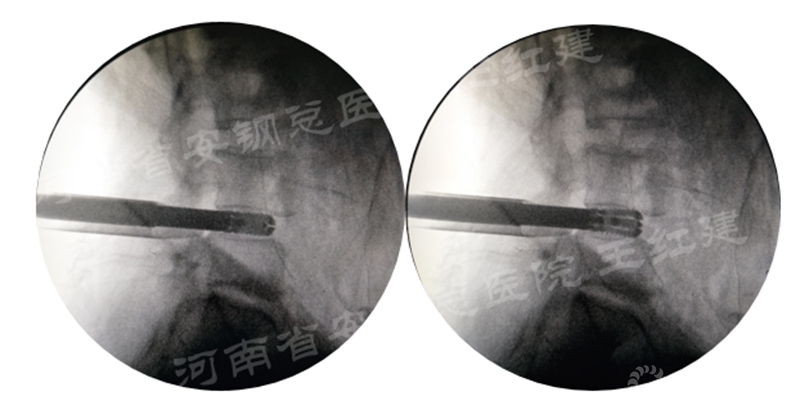

四、经皮螺钉技术固定

在固定的步骤可以先期进行经皮螺钉置入,再进行融合器的置入,进而实现充分固定。

椎弓根植入加压固定

单边椎弓根植入加压固定

双侧椎弓根植入加压固定

手术步骤:先期经皮螺钉置入、再进行融合器的置入